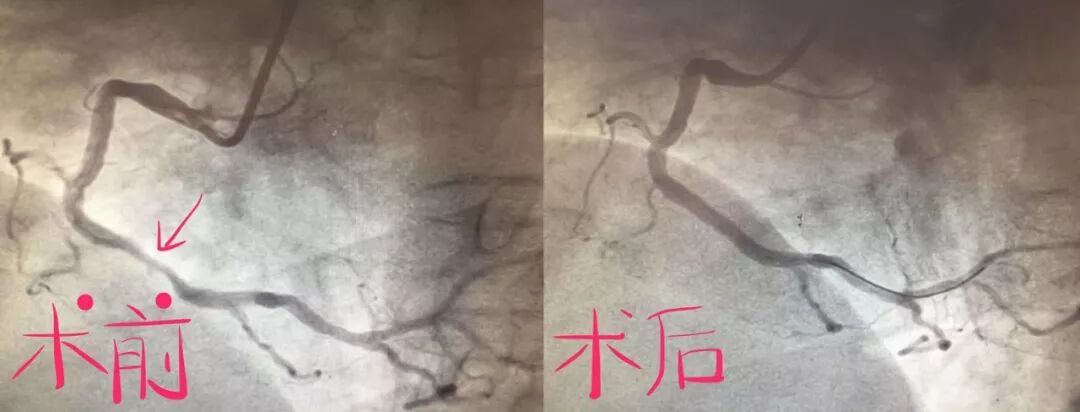

8个月前,六十多岁的吴大娘因反复胸痛入院,行冠脉造影检查后诊断为冠心病,心绞痛,根据造影结果在右冠状动脉植入支架一枚,左前降支轻度狭窄未处理,术后2个月患者症状未再发作。

但近6个月来,患者因反复发作胸痛、心慌及左侧肩背部、上腹部不适,行心电图检查提示前壁心肌缺血,给予对症处理后症状仍反复发作,患者由此产生了较大的心理压力。

心内科二病区高希春主任医师结合患者心电图及冠脉造影分析后,决定给予运动负荷心肌核素灌注显像检查,结果提示未见心肌缺血表现,从而明确了诊断,为患者解除了思想负担。

冠状动脉造影是了解冠状动脉是否狭窄等形态学改变的最好方法,但它不能反映心肌局部的血流灌注与心肌细胞的活性;而心肌灌注显像可以评估患者心肌细胞灌注情况及活性,可以帮助确定缺血是可逆性还是不可逆性以及冠状动脉的储备功能,能够更好的辅助造影检查评估患者冠脉血流及心肌灌注情况。